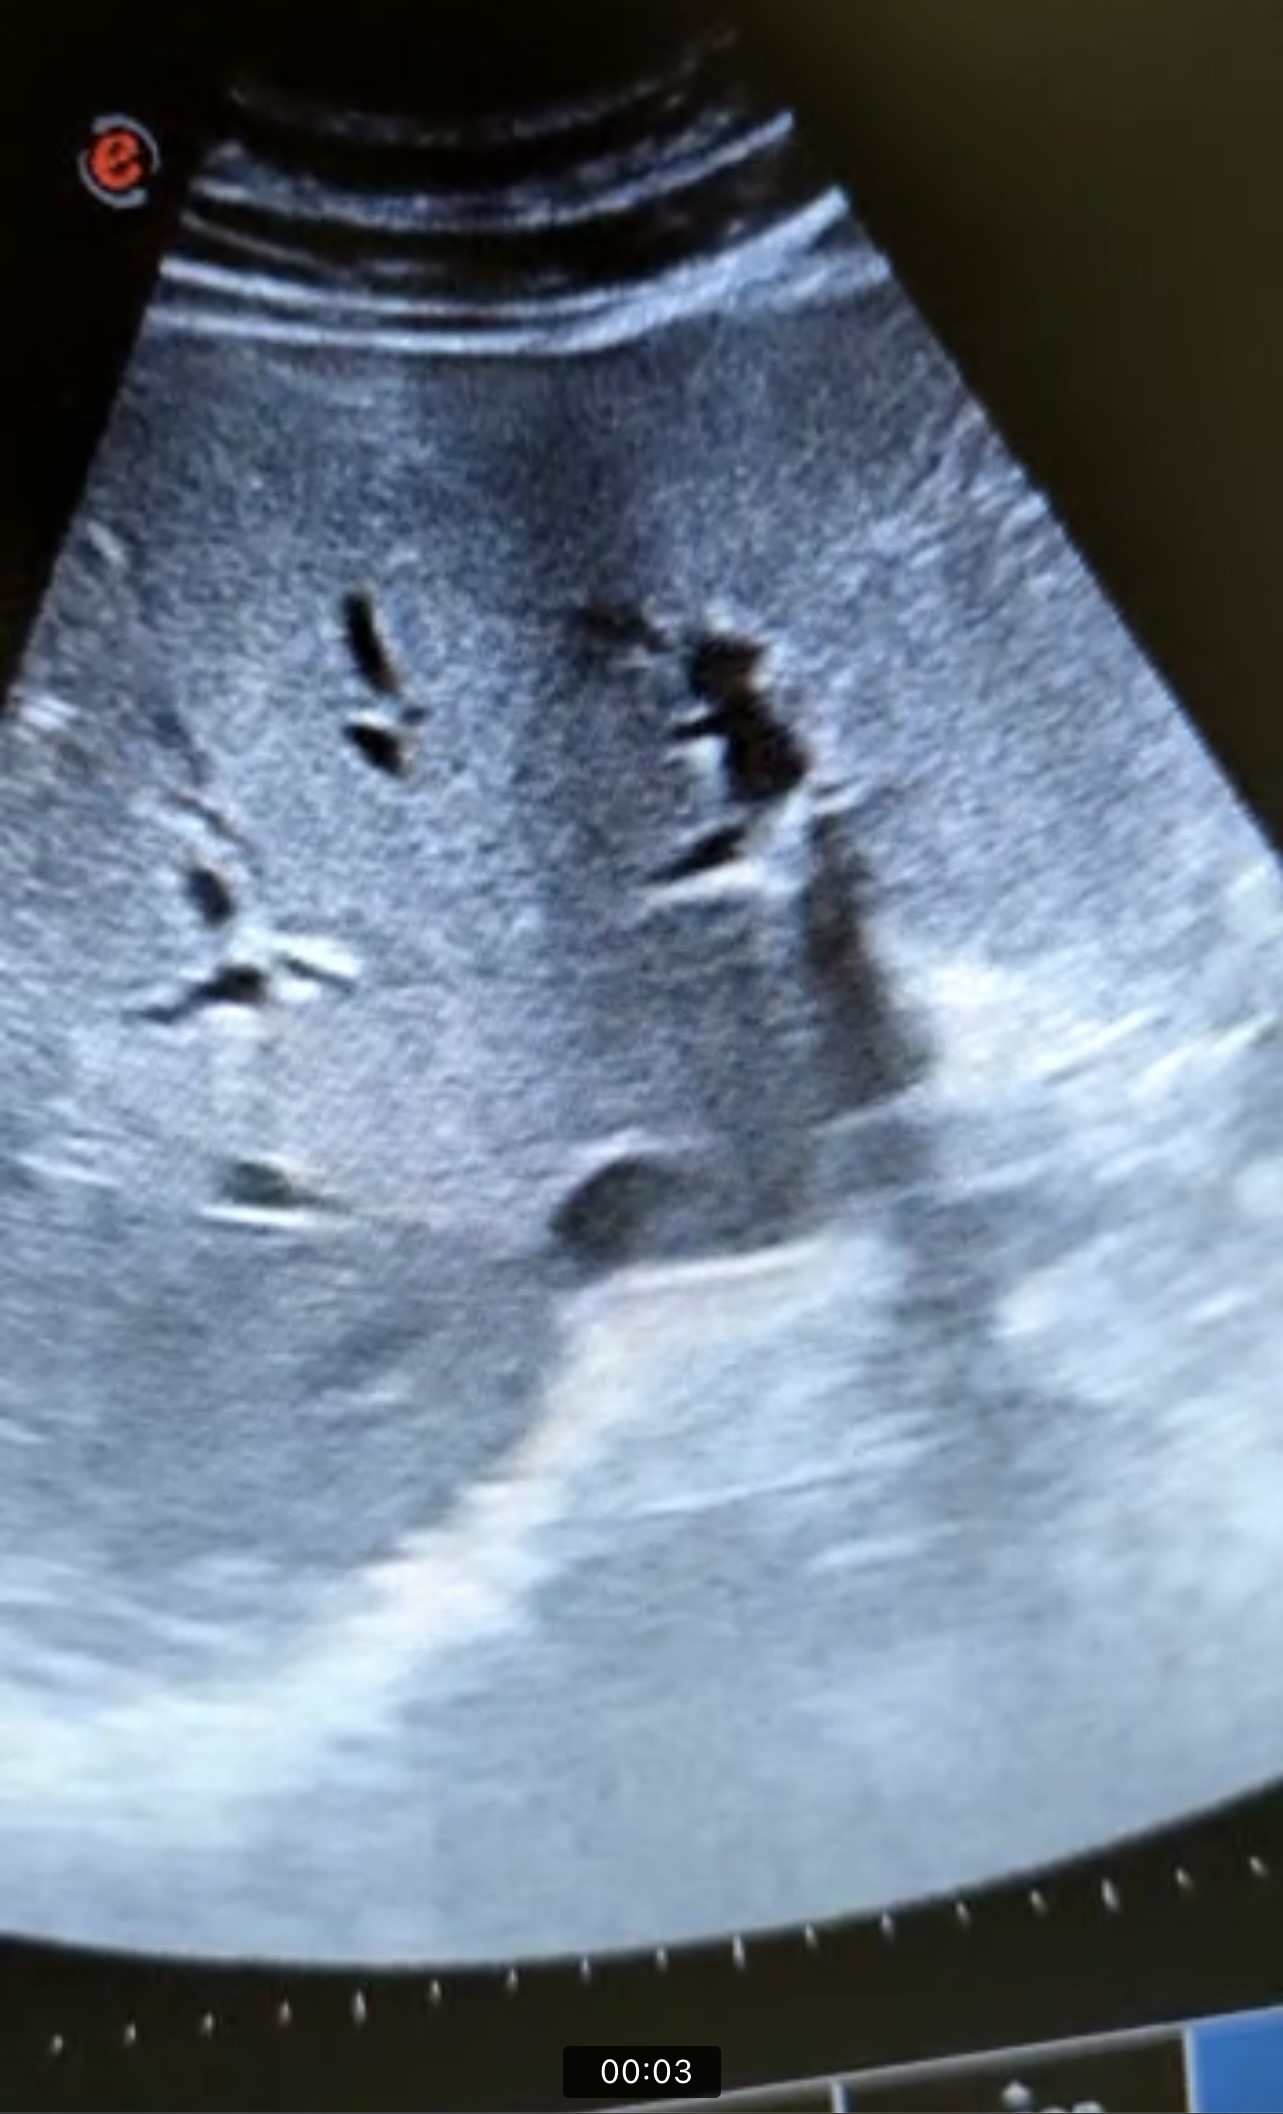

En la ecografía se observa ectasia de la vía biliar intrahepática conformando un patrón de doble carril.

Por los hallazgos ecográficos y de la exploración física se decide derivar a urgencias del hospital de referencia ante la sospecha de colecistitis aguda vs coledocolitiasis. En urgencias se realiza ecografía con resultado concordante con la realizada desde Atención Primaria.